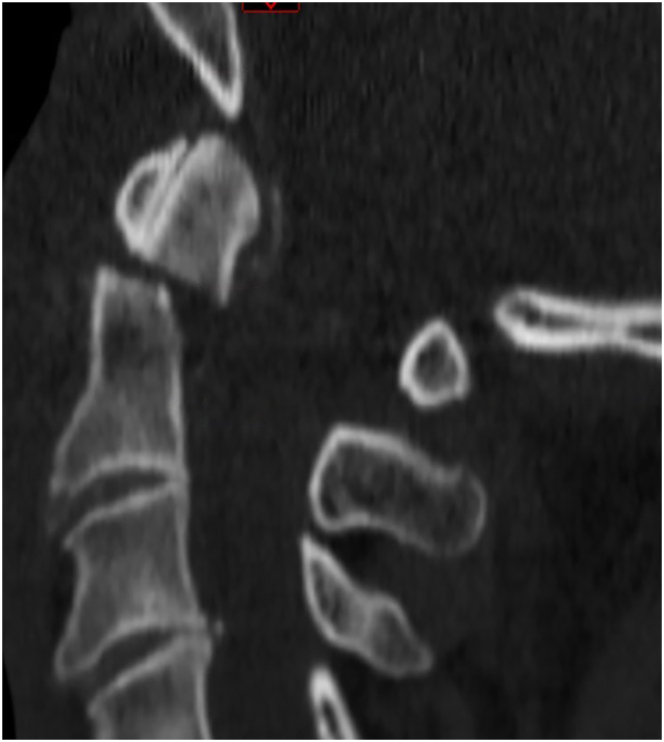

Introduction: Controversy exists regarding the optimal management of type II odontoid fractures in the geriatric population. The objective of this study was to determine the current treatment patterns of spine surgeons for geriatric patients (≥70 years) with type II odontoid fractures.

Results: A total of 154 responses were collected from 119 neurosurgeons (77.8 %) and 34 orthopedic surgeons (22.2 %). Participants were predominantly from Europe (92.7 %), and 63.2 % have been in practice >10 years. Fracture displacement, comorbidities and age were the most influential factors for decision-making. For non-displaced fractures, 78.8 % of respondents recommended conservative treatment for patients aged 70-80 years, and 83.7 % for those aged 80-90 years. For displaced fractures, 70.9 % preferred surgery for patients aged 70-80 years, whereas this preference decreased to 47.9 % for those aged 80-90 years. Posterior C1-2 fixation was the most common technique for 67.3 % of respondents, and 48.3 % prescribe a collar postoperatively. 51.3 % routinely order CT imaging postoperatively to assess for bony fusion. For conservative treatment, 59.3 % prescribe an external orthosis for 3 months.